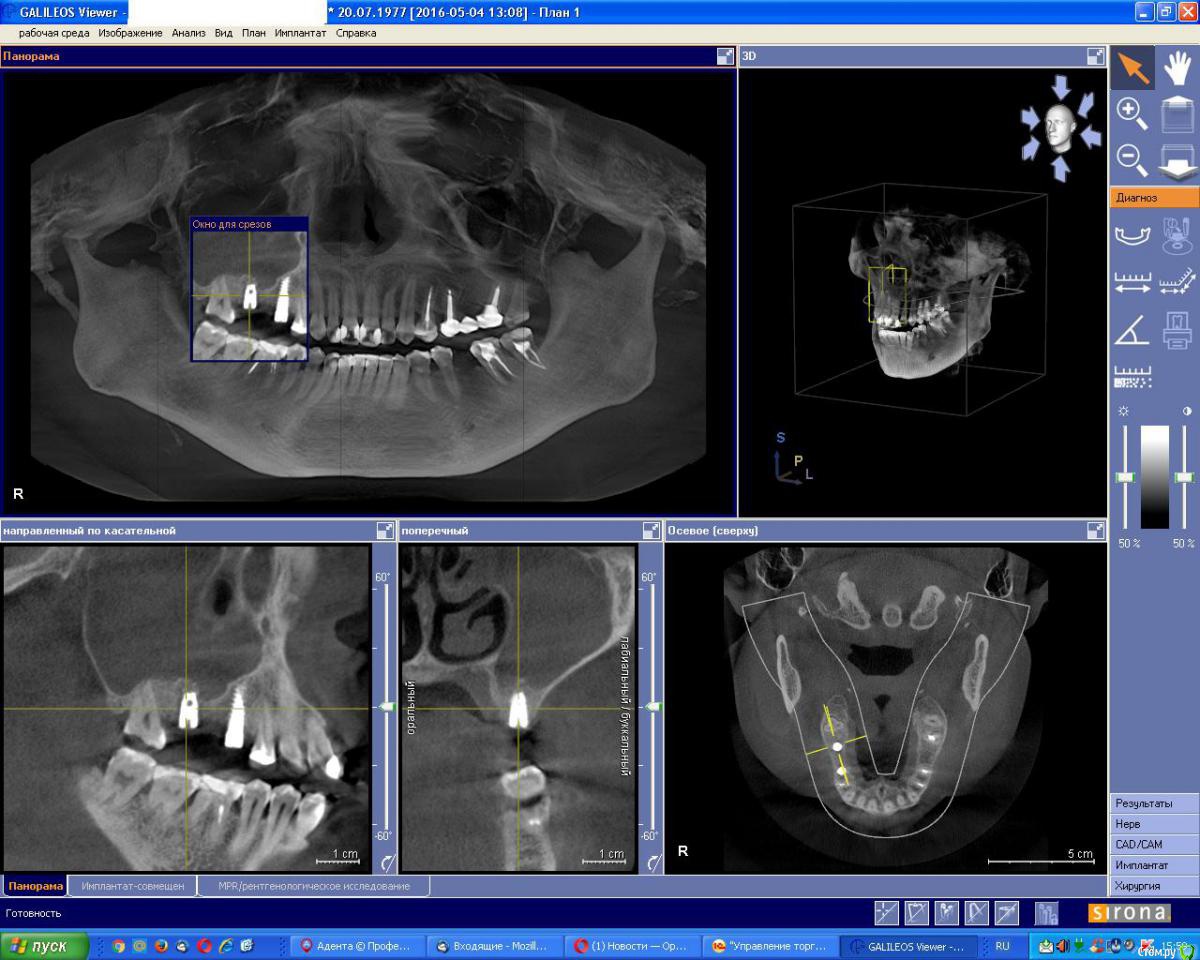

an_ver Опубликовано 26 января, 2017 Поделиться Опубликовано 26 января, 2017 (изменено) Фигня такая была...после синуса закрытого (наверно графт стрельнул), после долгих мытарств по Лорам, проколов и антибиотиков, залез сам, имплант удалил, графт выскоблил, все грануляции и хрень всякую почистил, в пазуху промыл стерильным физ.р-ом (долго,мыл), оросил дексой, в дыру пупочный шланг, детский))), конец наружу подшил ( 1см),чтоб не выскочил, и потом антибиотики внутрь, и мыть,мыть,мыть...физ.раствором,чтоб из носа побежало...на 3 -4 день, чистая вода побежала, на 7 скинул трубку, через 3 месяца вроде поставил шуруп, но рядом..и отстучался по Ильгаму,без графта...все хорошо Изменено 26 января, 2017 пользователем an_ver 3 Ссылка на комментарий

an_ver Опубликовано 26 января, 2017 Поделиться Опубликовано 26 января, 2017 История в картинках 4 Ссылка на комментарий